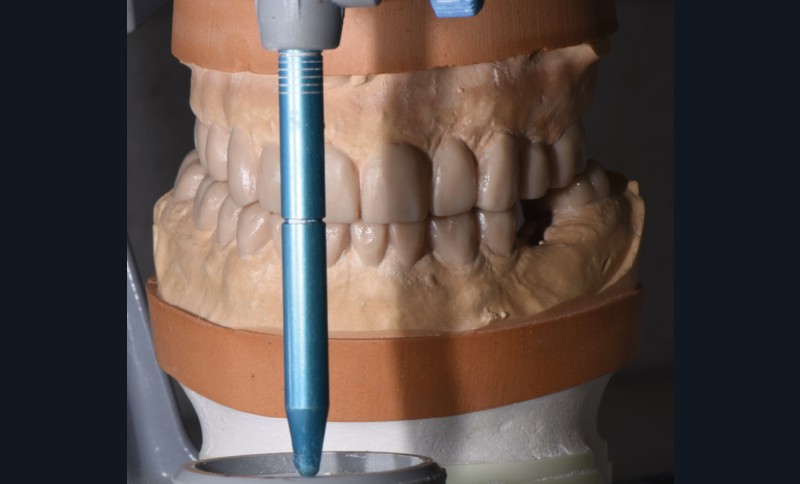

Au vu du contexte para-fonctionnel et de l’étendue de la perte tissulaire, des coiffes périphériques minimalement invasives ont été choisies afin de restaurer l’esthétique et la fonction. Actuellement, aucun consensus n’est fait sur le choix du matériau d’infrastructure à privilégier. Les matériaux hybrides usinables présentent des propriétés mécaniques, physiques et biologiques intéressantes en contexte d’usure sévère (e.g., module d’élasticité, résistance à la propagation de fêlures, facilité de réintervention). Une réhabilitation globale avec remontée de dimension verticale d’occlusion (DVO) par l’intermédiaire de coiffes composites renforcés en nano-céramiques est décrite.

Les auteurs remercient le laboratoire Bertin, Bordeaux, ainsi que Madame Delphine Bibard pour leur précieuse aide dans la réalisation de ce cas.